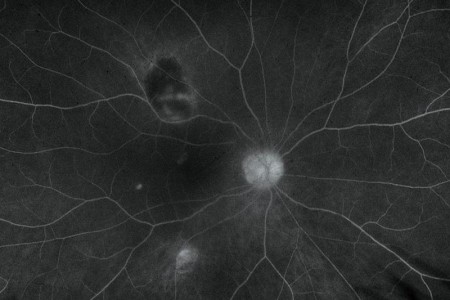

Fluorescein Angiography